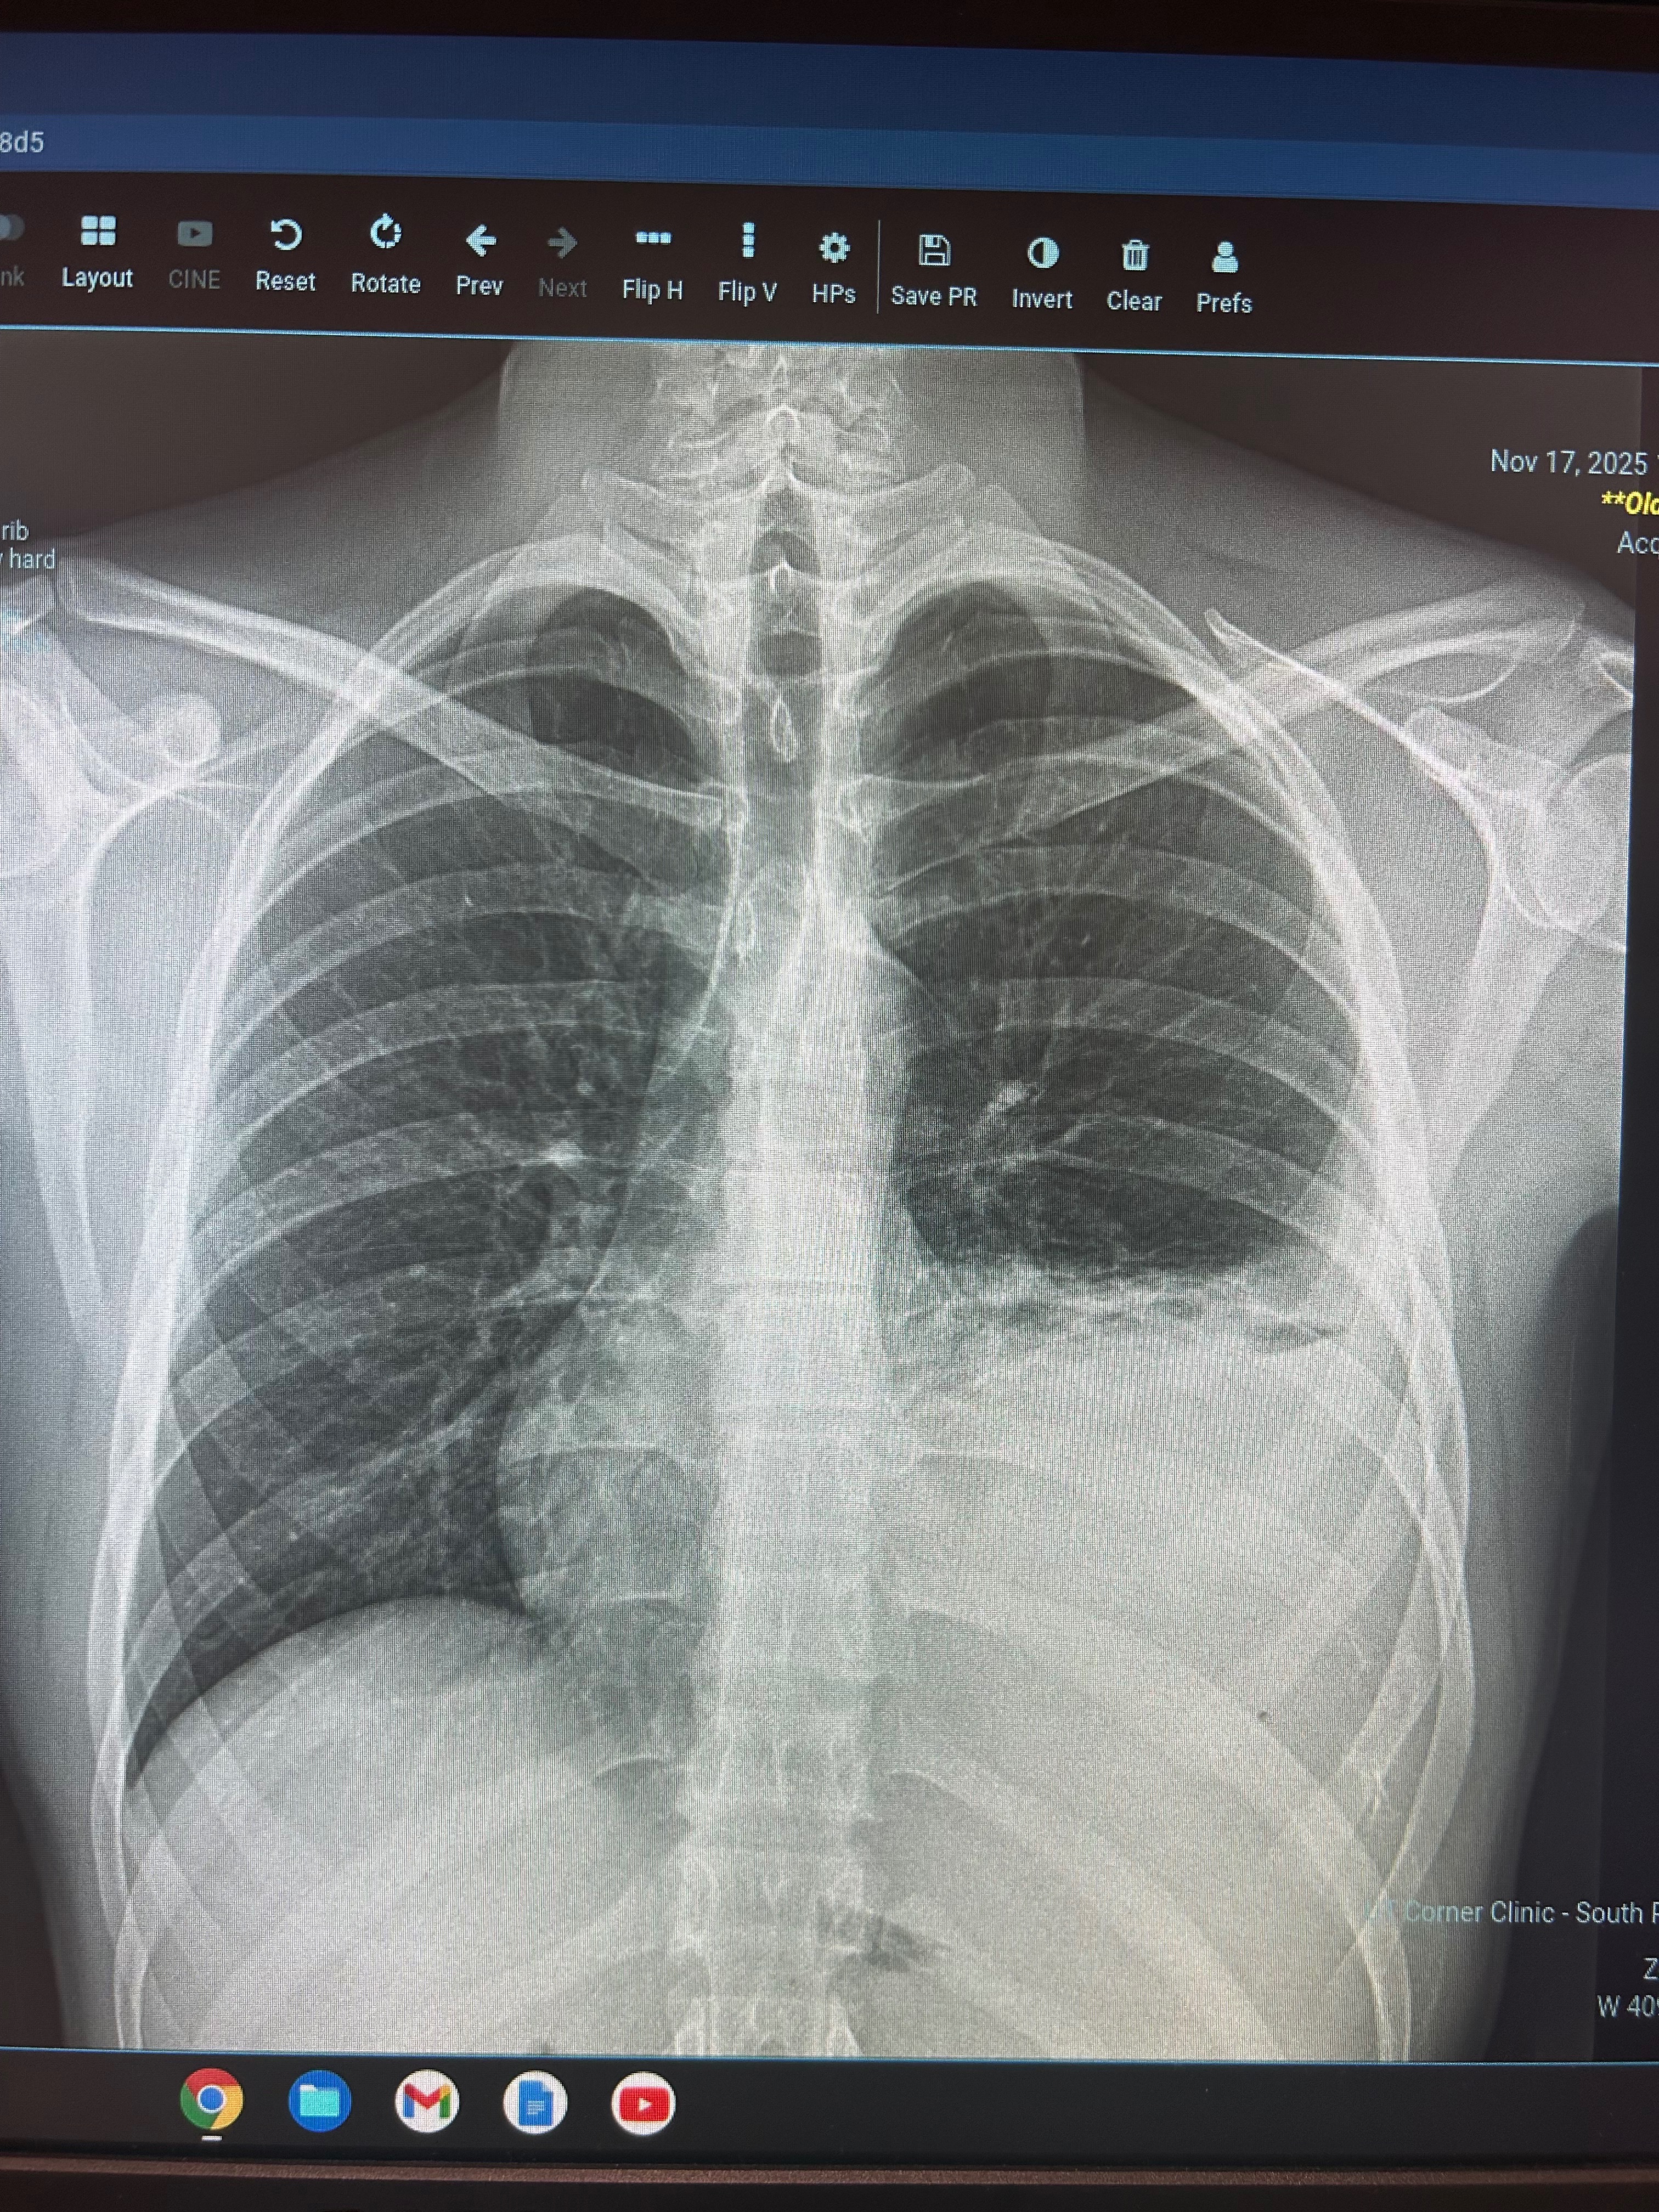

The Campbell family recently received the devastating news that their oldest son, Kody, who is only 19 years old, has been diagnosed with sarcoma cancer. This aggressive tumor has already destroyed one of Kody’s rib bones and is overtaking his lung, making it difficult for him to breathe and causing him to retain a significant amount of fluid. The suddenness and severity of Kody’s diagnosis have turned the Campbell family’s world upside down, bringing with it not only emotional pain but also overwhelming financial challenges.